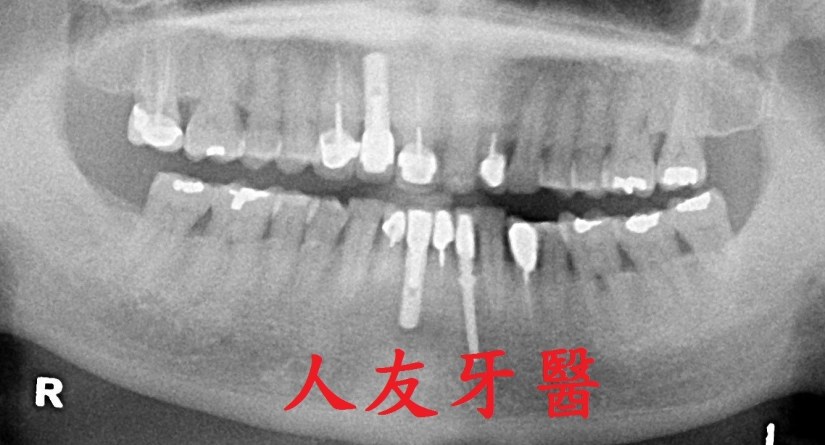

植體周圍炎牙齒從外表看不出來,需從x光片才能看出來,為避免造成植體周圍組織發炎,甚至破壞到周遭骨頭,平時應注重牙齒清潔保養,選擇刷毛軟的牙刷清潔 , 搭配牙間刷去清潔牙縫 , 並定期回診檢查,確保牙齒健康。

但尚未影響到硬組織,被稱為植體周圍黏膜炎;若已破壞到周遭骨頭,被稱為植體周圍炎。若周遭骨被破壞,最後可能造成植體失敗,需要移除,植牙等於做了白工。分析造成植體周圍疾病的原因,主要是細菌,如牙菌斑;咬合力量過大、牙套完成時殘留的黏著劑未清潔乾淨、製作不當的牙套也會。